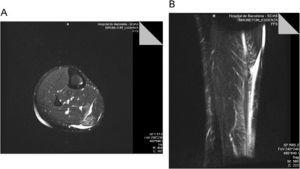

DESCRIPCIÓ DEL CASJugador de bàsquet professional que durant la temporada 2008–09 pateix en un entrenament una estrebada muscular a la cama dreta durant una acció defensiva, quan passava dun estirament de la cama per frenar el cos cap enrere, a una flexió plantar brusca per tirar al cos endavant . Durant les primeres 48h es fa tractament tipus RICE (rest, ice, compression, elevation) i se li va permetre caminar, si bé ho fa amb dificultat. Es realitza un primer estudi ecogràfic ales 12h que determina una lesió del m. bessó intern amb un petit hematoma mio-fascial. Davant la sospita clínica i ecogràfica duna lesió del m. soli aconsellem un estudi mitjançant ressonància magnètica (RM) a les 24h de produir-se la lesió . Lestudi per RM, realitzada mitjançant sistema de 1,5T (Magnetom Essenza, Siemens Healthcare), és informada de lesió tipus tennis leg (figura 1).

Figura 1. a) Imatge axial potenciada en T2 obtinguda en la porció distal del bessó intern; mostra líquid dins de la unió mio-fascial entre el m. Soli i el m. Bessó intern i en la unió mio-tendinosa distal del bessó intern. També saprecien focus de hipersenyal dins del bessó intern, que presenta una discreta retracció i del m. Soli. b) imatge coronal stir dels bessons que mostra líquid en la unió miotendinosa distal del m. Bessó intern i edema intramuscular del m. Soli i m. Bessó intern.